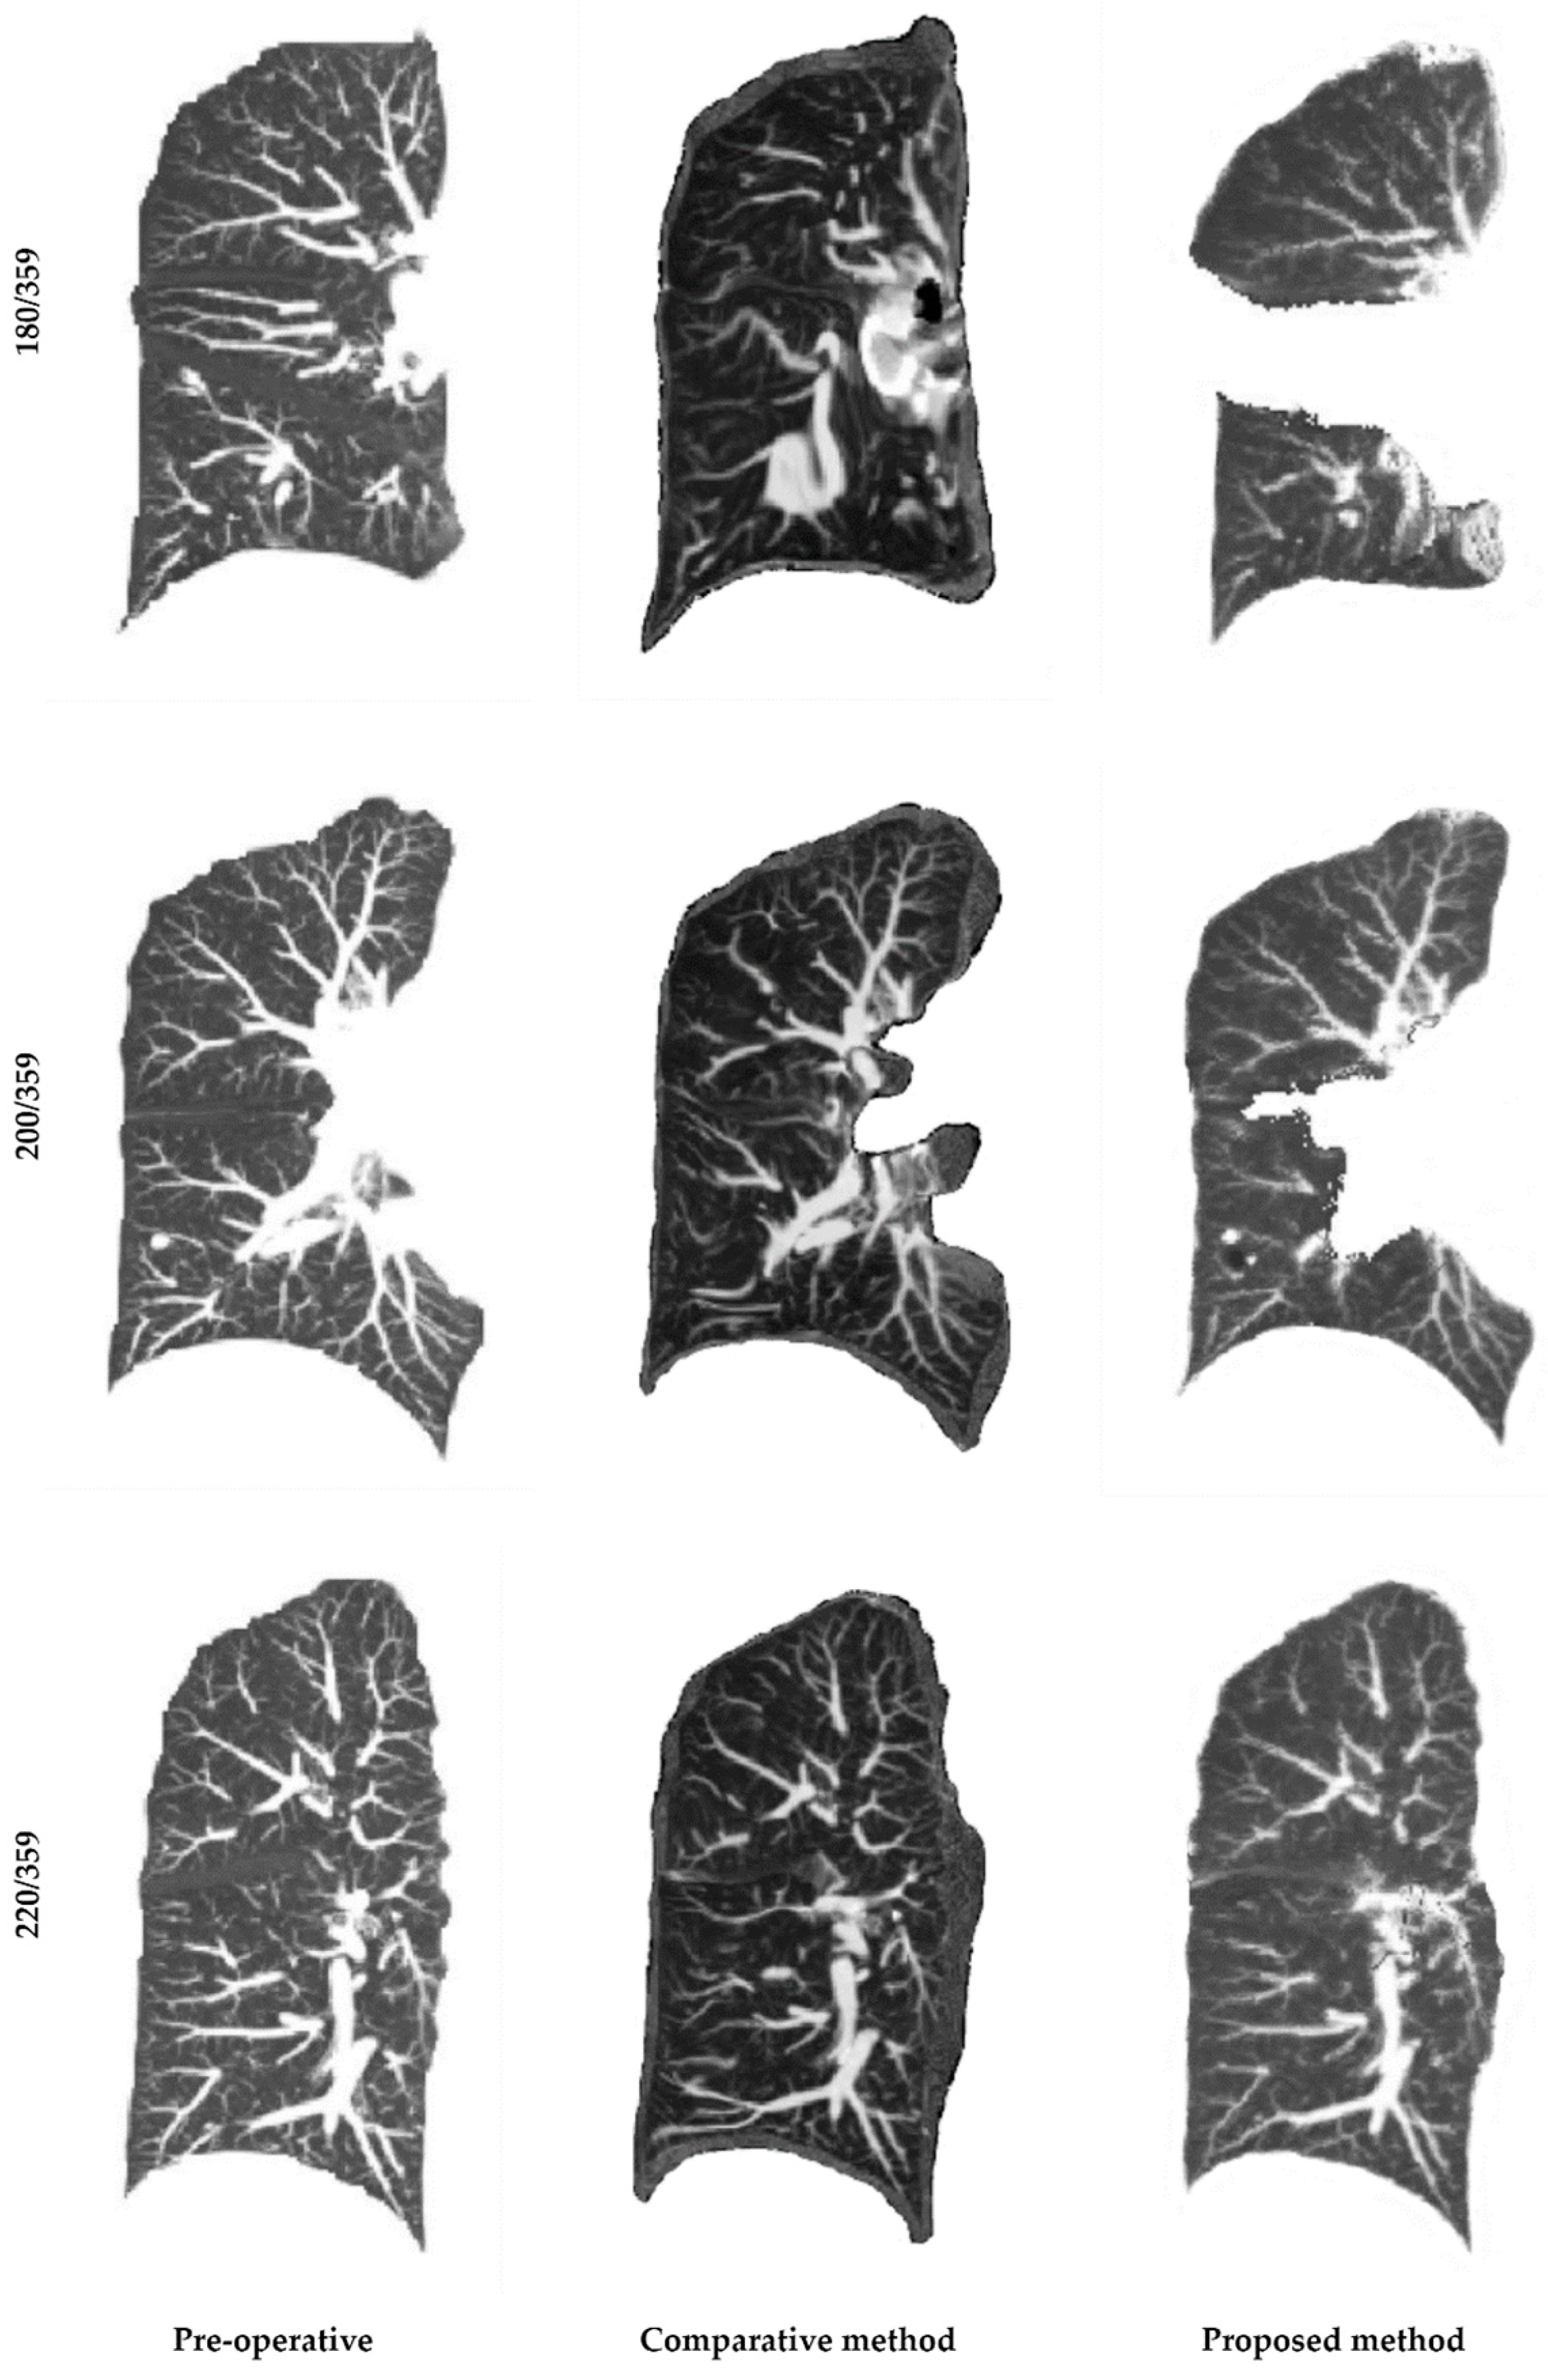

3.3. Comparison of Image Registration Methods